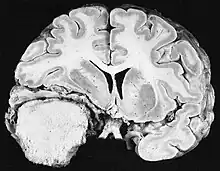

Cross section of a meningioma displacing the underlying brain.

Sources of ionizing radiation include medical imaging, and radon gas. Ionizing radiation is not a particularly strong mutagen.[74] Medical use of ionizing radiation is a growing source of radiation-induced cancers. Ionizing radiation may be used to treat other cancers, but this may, in some cases, induce a second form of cancer.[74] Radiation can cause cancer in most parts of the body, in all animals, and at any age, although radiation-induced solid tumors usually take 10–15 years, and can take up to 40 years, to become clinically manifest, and radiation-induced leukemias typically require 2–10 years to appear.[74] Radiation-induced meningiomas are an uncommon complication of cranial irradiation.[79] Some people, such as those with nevoid basal cell carcinoma syndrome or retinoblastoma, are more susceptible than average to developing cancer from radiation exposure.[74] Children and adolescents are twice as likely to develop radiation-induced leukemia as adults; radiation exposure before birth has ten times the effect.[74]